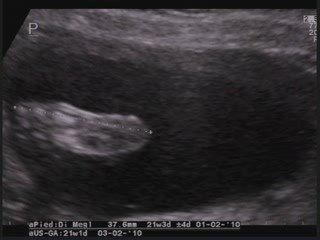

Difetto del setto atriale tipo ostium primum